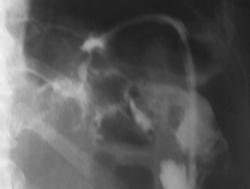

помогите разобраться имеется ли свищ толстой кишки

Как представляекся - оперативное вмешательство на желудке? Сейчас контрастной вещество в основном контрастировало развитую систему свищевых ходов в левом поддиафрагмаальном пространстве. Считаю, что сообщение с просветом поперечной ободочной кишки есть, но основная масса контрастного вещества располагается рядом с нисходящей кишкой. Доказательств  сообщения ходов с протоками панкреас не видно, но она в таких ситуациях принимает участие очень часто... Попытался бы применять встречное контрастирование - все повторить совместно с ирригоскопией, но гарантии в таких случаях не даст никто. Ищи - свищи....

Оперативное вмешательство  в октябре 2009г по поводу гемангиомы левой доли печени в объме резекции левой доли печени и хвоста поджелудочной железы, дренирование поддиафрагмального пространства. Сброса воздуха по дренажу никогда не отмечала.